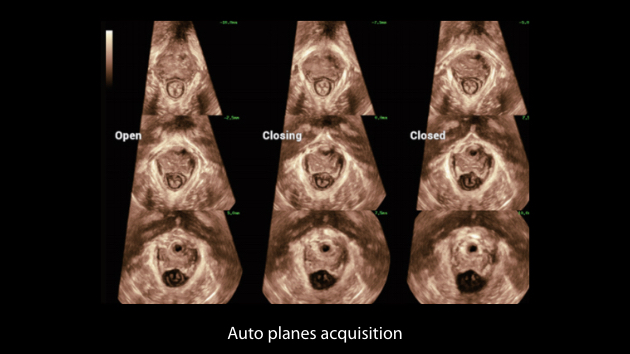

Le Nuewa?I9, con?u spÃĐcialement pour la santÃĐ de la femme et les soins nÃĐonataux, offre une expÃĐrience entiÃĻrement nouvelle gr?ce aux innovations dont il est dotÃĐ, tant à lâintÃĐrieur quâà lâextÃĐrieur. Ces innovations sont dÃĐveloppÃĐes sur la base d'une comprÃĐhension approfondie de scÃĐnarios cliniques complexes, fournissant des rÃĐponses prÃĐcises et adaptÃĐes ainsi qu'une efficacitÃĐ exceptionnelle et une expÃĐrience utilisateur remarquable.

La plate-forme ZST+?est une innovation extraordinaire, reprÃĐsentant une ÃĐvolution de lâimagerie ultrasonore. Elle transforme la formation conventionnelle de faisceaux en un traitement basÃĐ sur les canaux de donnÃĐes. Elle repousse les limites de lâimagerie conventionnelle et du compromis entre rÃĐsolution spatiale, rÃĐsolution temporelle et uniformitÃĐ tissulaire en offrant une qualitÃĐ dâimage exceptionnelle pour des solutions dâimagerie infinies et en constante ÃĐvolution.